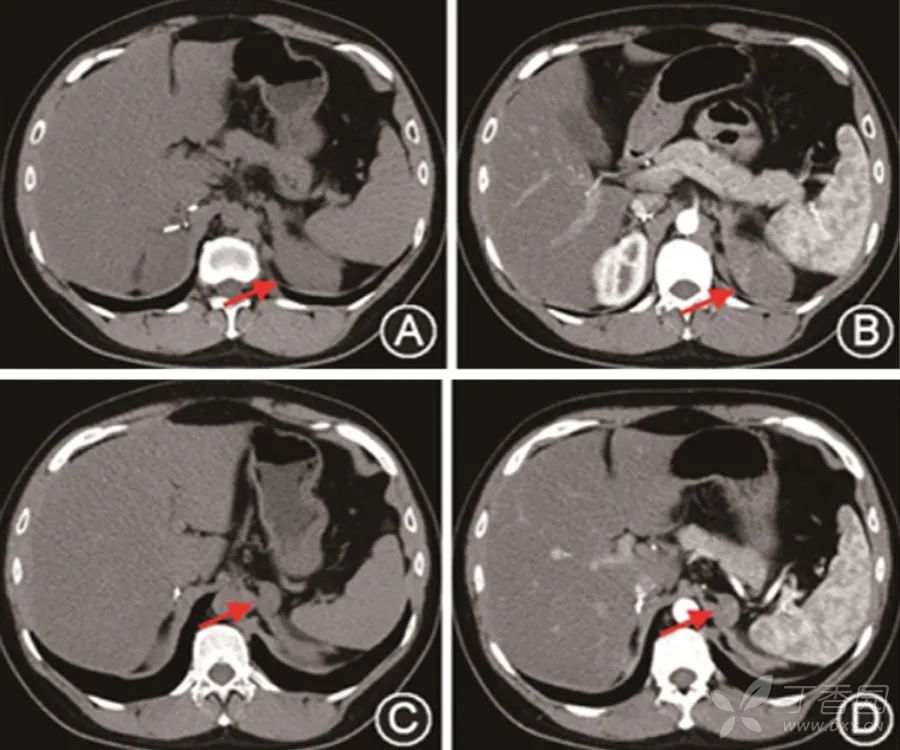

2年前,意外发现右侧肾上腺占位,并行手术切除。

半年前,再次意外发现左侧肾上腺2个占位,手术切除较大占位。

随访过程中发现左肾上腺未切除占位增长快速。

给予泼尼松睡前口服。定期复查肾上腺CT,肾上腺占位无进一步增长。